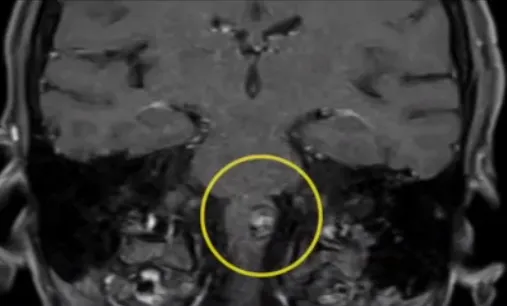

延髓海綿狀血管瘤

術(shù)后核磁可以確認已完全切除病變。術(shù)后3年,乙女士無新的神經(jīng)功能缺損或復(fù)發(fā)。改良Rankin評分由術(shù)前的中度殘疾,需部分幫助轉(zhuǎn)變?yōu)橥耆珶o癥狀,與正常人無異。

影像